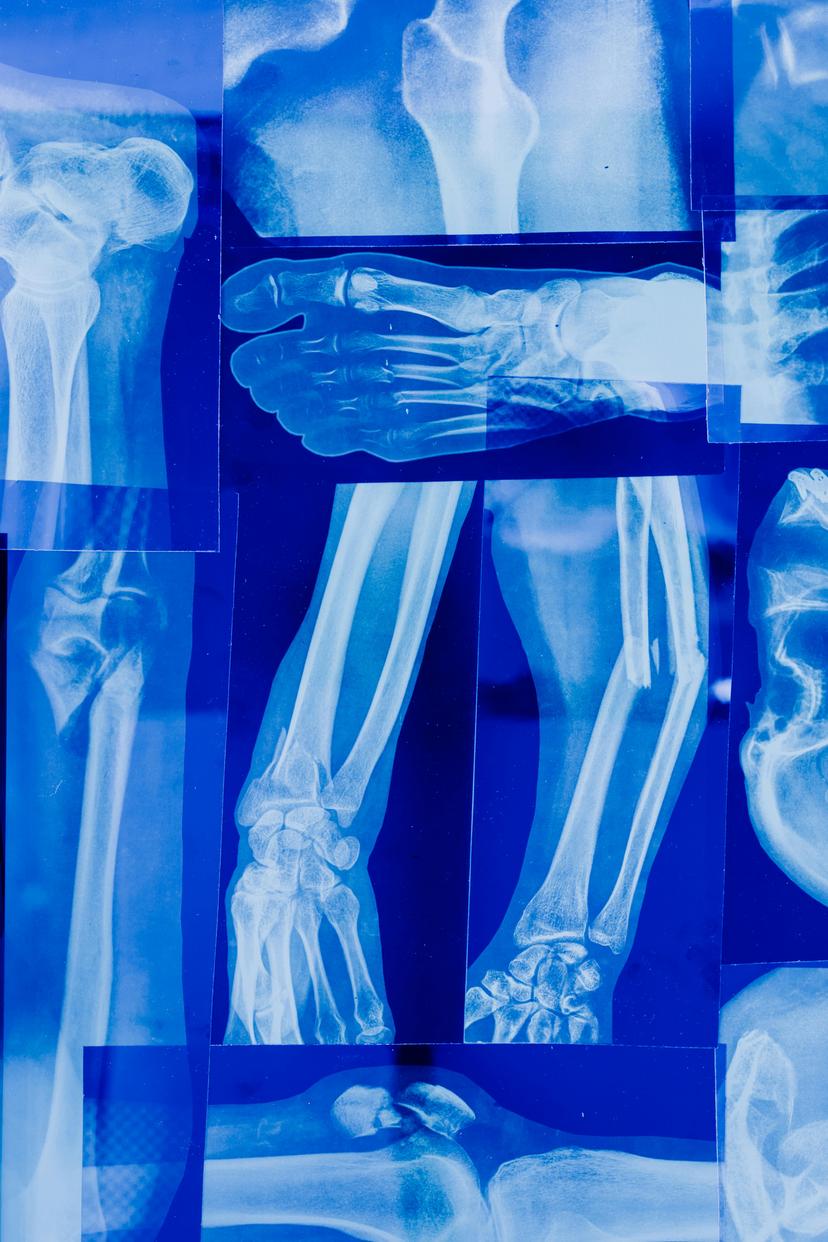

Advanced Orthopedic Treatments Available in the UK

The UK is a leader in orthopedic care, offering a wide range of advanced treatments that incorporate cutting-edge technology and highly specialized techniques. Here’s a detailed look at some of the most advanced orthopedic treatments available in the UK: